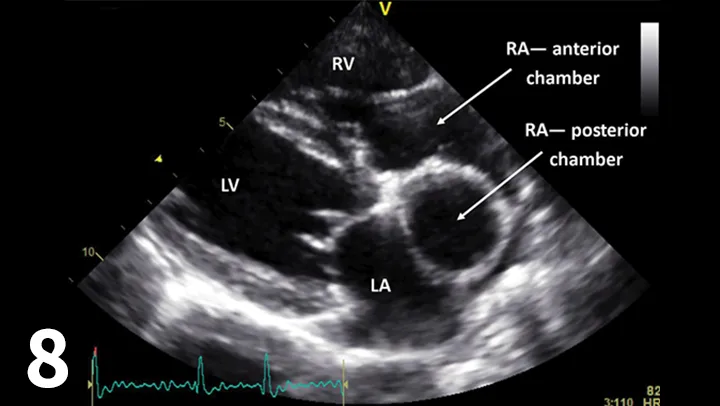

Figure 8.

Right-sided long-axis view showing the 2 chambers of the right atrium (RA) with the left and right ventricles. (Ao = aorta; LA = left atrium)